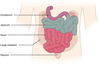

Label the following components of the alimentary canal: